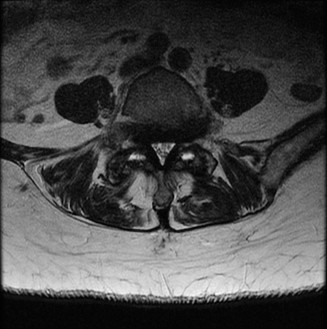

Magnetic Resonance Imaging and the Posterior Ligamentous Complex

To definitively assess the integrity of the soft tissue stabilizers and the neural elements, a Magnetic Resonance Imaging (MRI) scan without contrast was performed. Historically, textbooks propagated the "50-50-25 rule," suggesting that a burst fracture was inherently unstable if it exhibited >50% canal compromise, >50% loss of vertebral body height, or >25 degrees of kyphosis. Modern spine trauma surgery has largely debunked this rigid radiographic dogma. We now understand that these bony metrics alone do not dictate mechanical instability. The true arbiter of stability is the Posterior Ligamentous Complex (PLC).

The MRI, particularly the Short Tau Inversion Recovery (STIR) and T2-weighted sagittal sequences, provided the definitive diagnosis. The images demonstrated profound hyperintensity and discontinuity of the ligamentum flavum, the interspinous ligaments, and the supraspinous ligaments at the T12-L1 level. The facet joint capsules were also disrupted, indicated by fluid within the joints. This complete failure of the PLC means the posterior tension band is gone. Regardless of the bony parameters, this spine cannot resist physiological flexion loads. If treated non-operatively, this injury will inevitably lead to progressive kyphosis, delayed neurological deficit, and intractable pain.